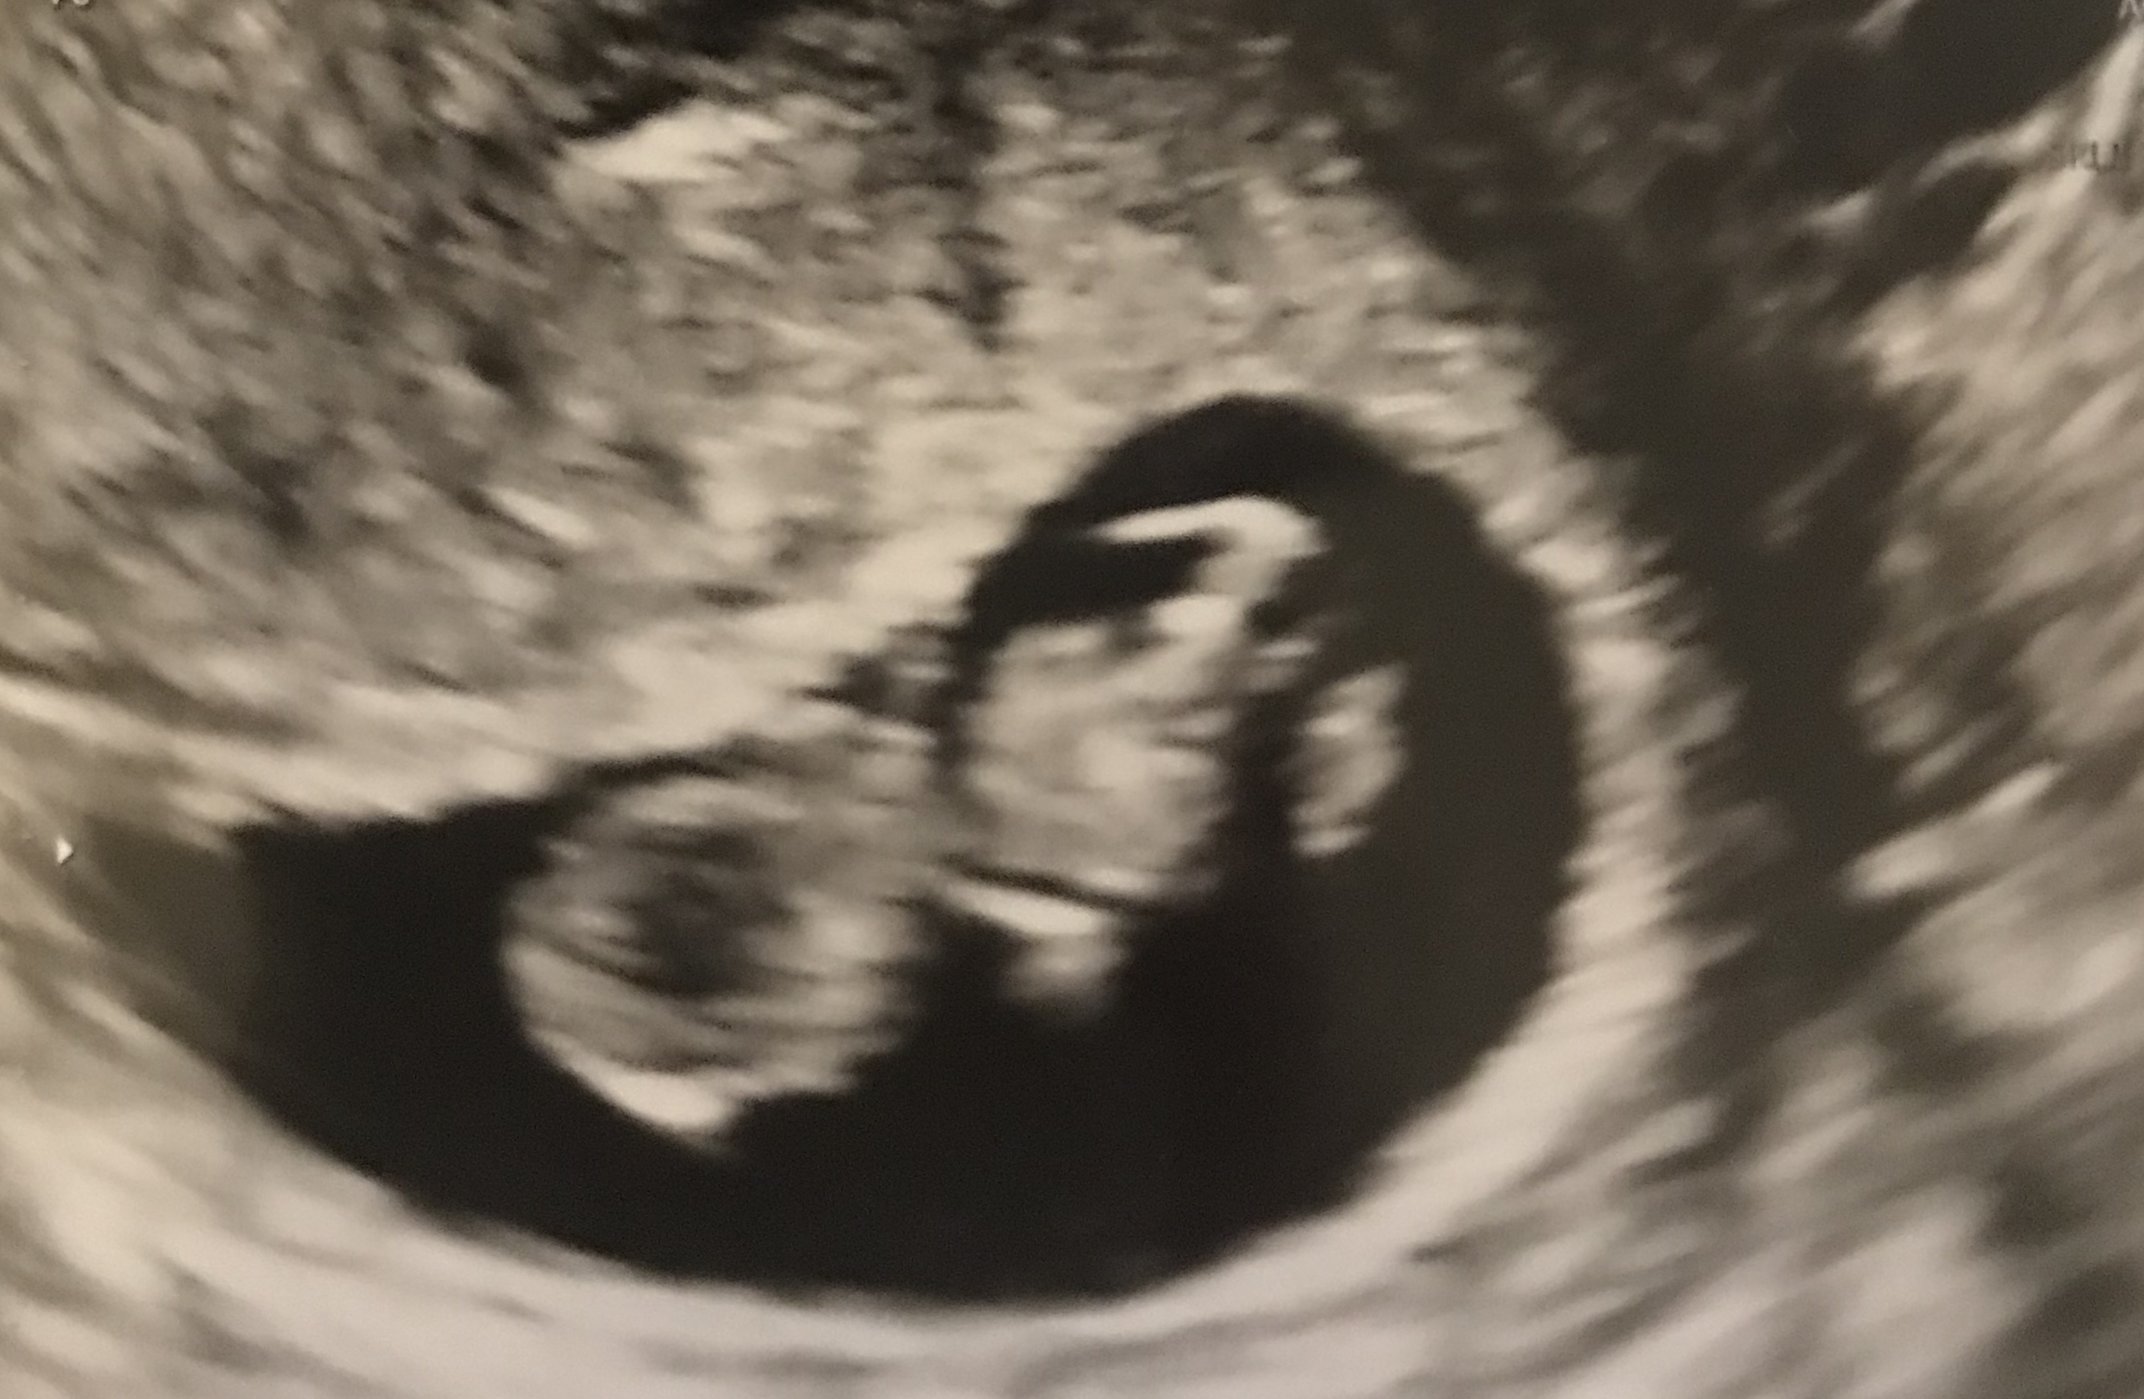

I've never shared a pic before so hope I did it right. Shock of my life last week when we saw 2 babies (di/di twins) measuring on track at 6w1d with flickering hearts, 119bpm and 120bpm. We see them again the 31st!